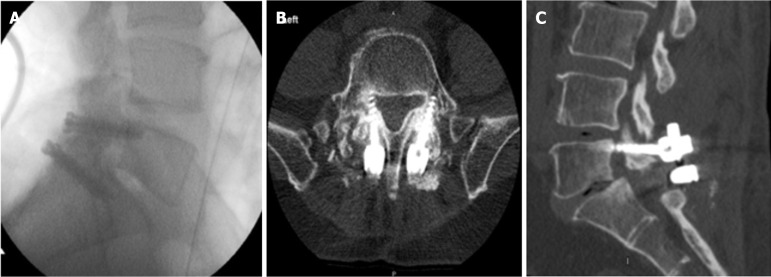

Abstract Image